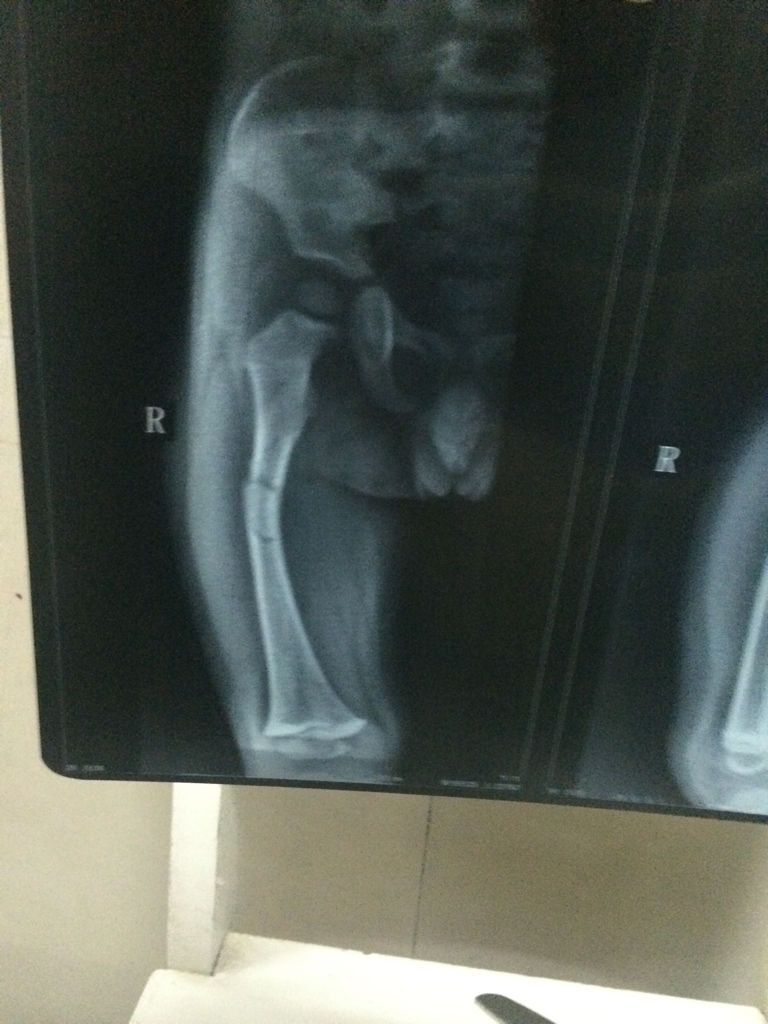

有骨科医生吗?求求你帮帮我,我儿子才一岁零九个月,于7月27日下午玩耍把右大腿骨折了,有点严重,现在在县城中医院就诊,医生叫我们保守治疗,但是我不懂,我看片子恢复得不怎么样,我怕儿子以后会有后遗症,现在好难过,求求你们救救我儿子,帮我给点建议!